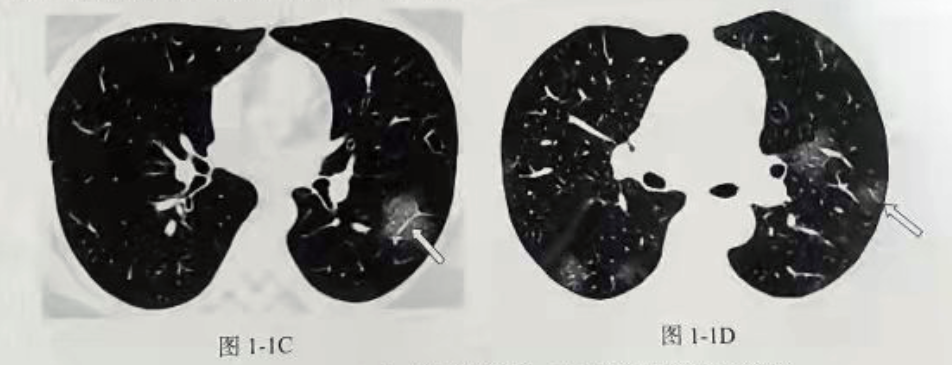

模型检测效果如下图:

对预测结果进行展示

可见模型对磨玻璃样病灶的细节分割并不是很好。但是这个项目的目地只是需要通过预测的mask结果在原图上画出病灶的轮廓,实现对病灶的检测和定位。告诉医疗那一层有磨玻璃样病灶,或者告诉医生那一层出现的磨玻璃样病灶面积是最大的。